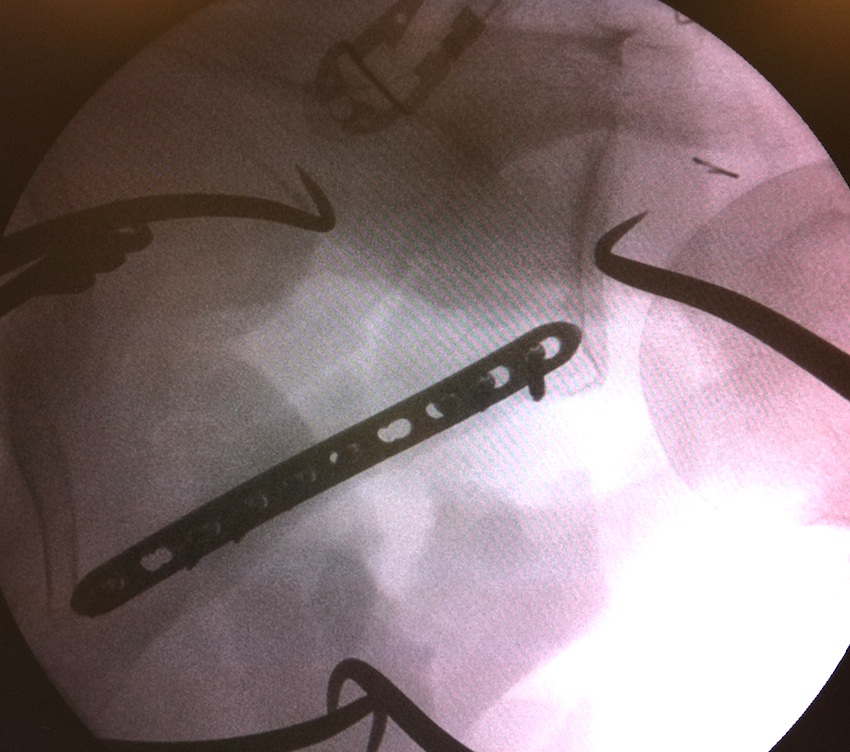

Case 1

- > 1 cm medial displacement

- ORIF via posterior / modified Judet approach

Case 2